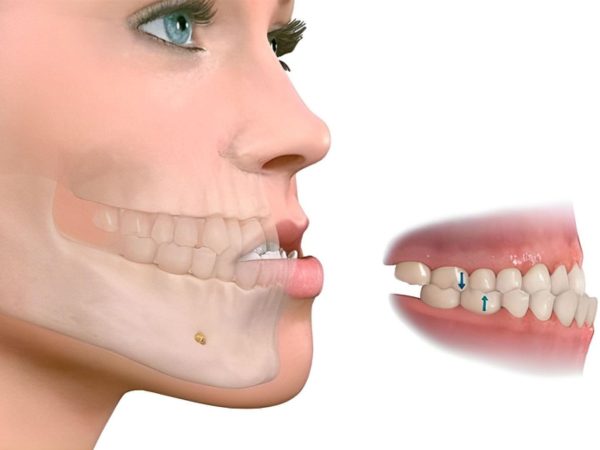

Phẫu thuật hàm móm (hay phẫu thuật chỉnh hình xương hàm móm) là phương pháp can thiệp trực tiếp vào cấu trúc xương hàm để điều chỉnh tình trạng sai khớp cắn do xương hàm dưới phát triển quá mức, khiến răng hàm dưới phủ ra ngoài răng hàm trên (móm).

Ở tuổi trưởng thành, khi xương hàm đã phát triển ổn định, niềng răng chỉ có thể tác động lên răng để sắp xếp lại vị trí và điều chỉnh khớp cắn hài hòa hơn giữa hai hàm. Niềng răng có thể giúp đưa khớp cắn về đúng tương quan sinh lý (hàm trên phủ ngoài hàm dưới), cải thiện khả năng ăn nhai và tính ổn định của khớp cắn.

Tuy nhiên, niềng răng hầu như không thể thay đổi cấu trúc xương hàm ở người trưởng thành, do đó phần thẩm mỹ góc mặt nghiêng (hô xương – móm xương – lệch mặt do xương) sẽ không thể cải thiện 100% chỉ bằng chỉnh nha. Trong những trường hợp khách hàng mong muốn cải thiện cả chức năng lẫn thẩm mỹ tối đa, đặc biệt là các vấn đề liên quan đến xương hàm, thì cần kết hợp phẫu thuật hàm. Phẫu thuật sẽ can thiệp trực tiếp vào cấu trúc xương, đưa hàm về vị trí chuẩn, từ đó tối ưu thẩm mỹ gương mặt và tạo nên khớp cắn ổn định lâu dài.

Móm do xương hàm dưới phát triển quá mức

Khi cấu trúc xương hàm dưới đưa ra trước vượt quá giới hạn sinh lý, làm xáo trộn khớp cắn và ảnh hưởng đến chức năng ăn nhai. Trong trường hợp này, niềng răng không mang lại hiệu quả vì nguyên nhân xuất phát từ xương, chứ không phải từ vị trí răng.

Nếu tình trạng khớp cắn ngược xuất phát từ xương hàm, niềng răng vẫn có thể đưa răng về vị trí hài hòa hơn, giúp khớp cắn cải thiện và chức năng ăn nhai, phát âm trở nên tốt hơn. Với những khách hàng chỉ cần ổn định khớp cắn và ưu tiên chức năng, chỉnh nha là lựa chọn phù hợp.

Tuy nhiên, ở các trường hợp mong muốn cải thiện thẩm mỹ góc nghiêng tối đa, đặc biệt khi có sai lệch xương hàm (hô – móm – lệch mặt do xương), thì cần kết hợp phẫu thuật hàm để đưa cấu trúc xương về đúng vị trí. Chỉnh nha sẽ giúp sắp xếp răng chuẩn trước – sau phẫu thuật, còn phẫu thuật hàm đảm nhiệm phần thay đổi cấu trúc xương, từ đó mang lại hiệu quả thẩm mỹ tối ưu nhất.